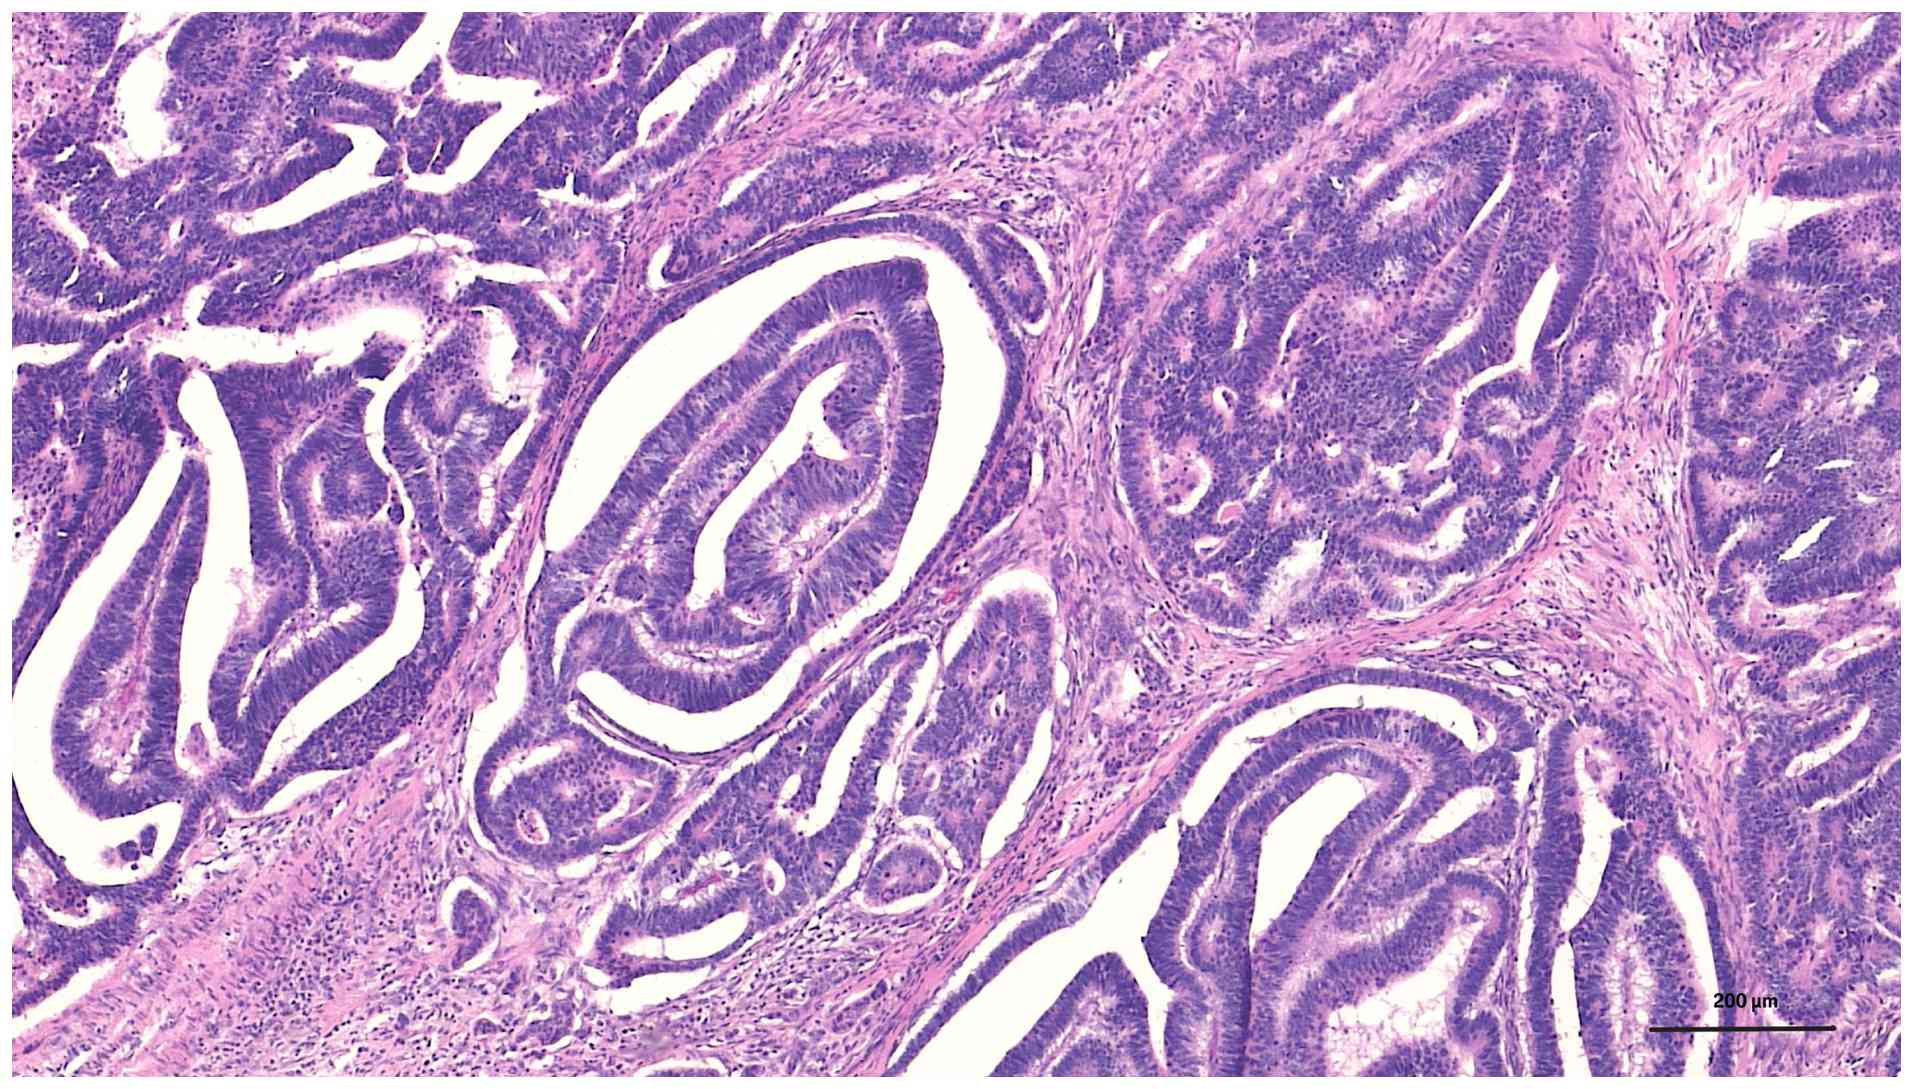

Given the extensive colonic polyposis and confirmed malignancy at the hepatic flexure, the patient underwent a subtotal colectomy with end-to-end ileorectal anastomosis. Postoperative histopathological analysis confirmed a moderately differentiated adenocarcinoma of the hepatic flexure, which was staged as pT3N0M0 (Stage IIA), along with >100 tubulovillous adenomas observed throughout the resected colon (Fig. 2B). Paraffin-embedded tissue sections were stained with hematoxylin and eosin (H&E) according to a standard protocol. Briefly, tissue samples were fixed in 10% neutral buffered formalin at room temperature (~22˚C) for 8 h before being embedded in paraffin. Sections 4-µm thick were cut using a microtome. H&E staining was performed with hematoxylin at room temperature for 10 min followed by eosin for 2 min. Histopathological examination revealed irregular dysplastic glands infiltrating into the submucosa and muscularis propria, accompanied by a prominent desmoplastic stromal reaction (Fig. 3). At higher magnification, the tumor was found to have an atypical glandular structure with nuclear pleomorphism, hyperchromasia and loss of normal glandular polarity within a fibrotic stroma, consistent with moderately differentiated adenocarcinoma (Fig. 4).

Histopathological examination at

high-power view demonstrating atypical glandular structures with

nuclear pleomorphism, hyperchromasia, and loss of glandular

polarity within a fibrotic stroma, consistent with moderately

differentiated adenocarcinoma (hematoxylin and eosin;

magnification, x400; scale bar, 200 µm.

Figure 4

Histopathological examination at high-power view demonstrating atypical glandular structures with nuclear pleomorphism, hyperchromasia, and loss of glandular polarity within a fibrotic stroma, consistent with moderately differentiated adenocarcinoma (hematoxylin and eosin; magnification, x400; scale bar, 200 µm.